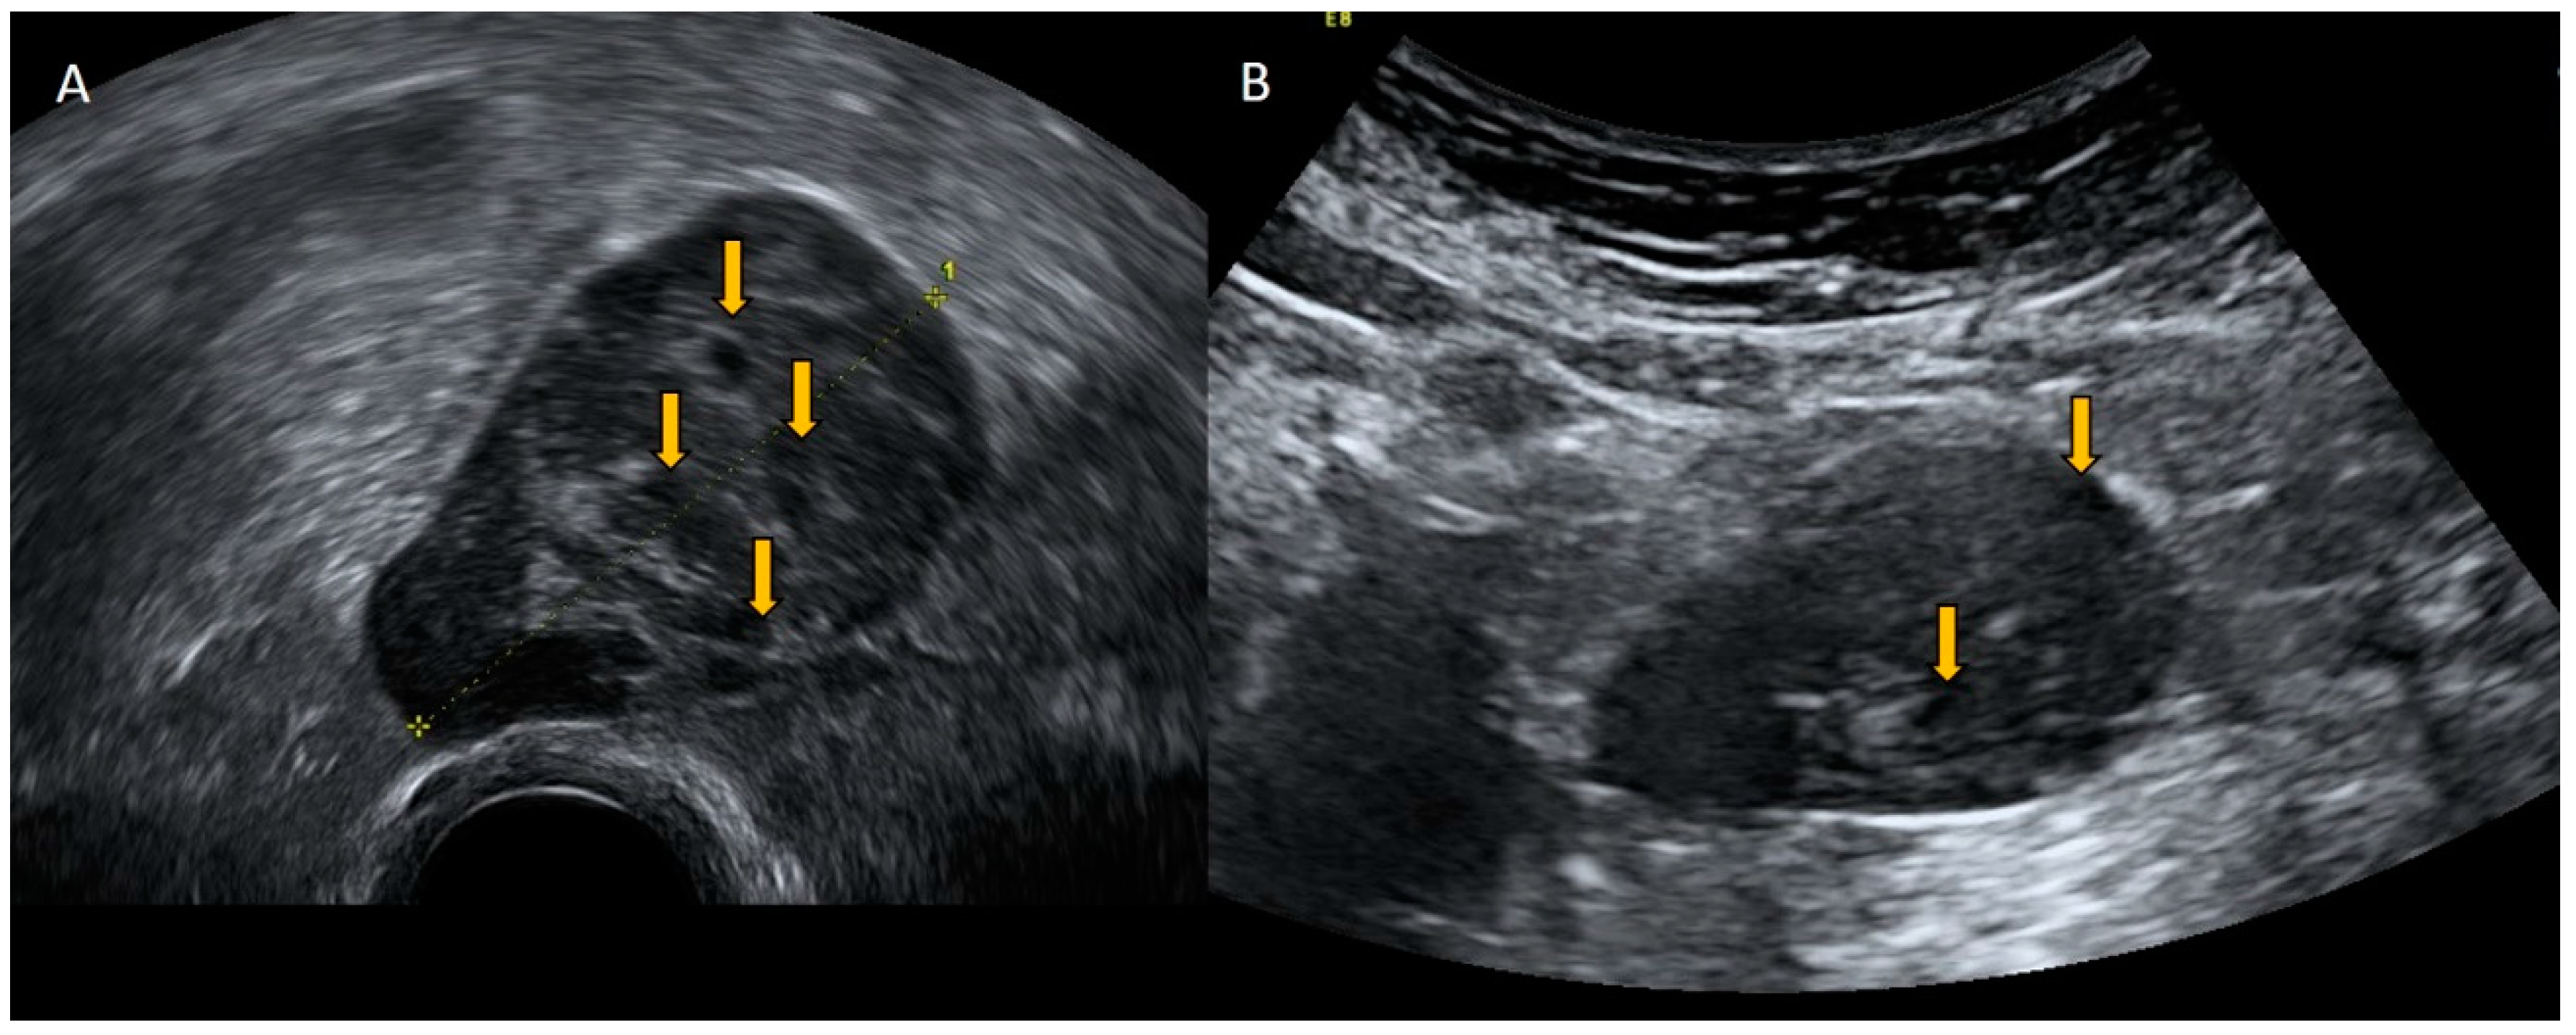

4.3. Aneurysm